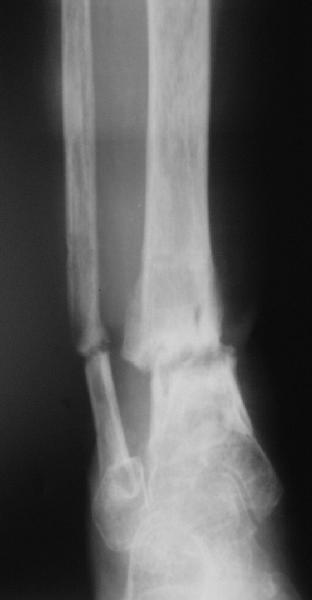

Глубокоуважаемые коллеги,Поступила женщина 72 лет. Полтора года назад - укушенная рана, перелом голени. Лечили аппаратом, не срослось. Долго не заживала рана.

Но вроде уже с полгода мягкие ткани закрыты. Спереди подпаянные рубцы. Есть приличная подвижность на уровне несращения. Картинки в приложении. Что предложите? Спсибо заранее.

Why the need for the Ilizarov if the nonunion is mobile? I would correct the deformity acutely with a fibular osteotomy if necessary to correct the

alignment and proceed with reamed IM nailing if there are no signs or history of infection. Minimum of 2 and preferably 3 distal locks, and put in a big enough nail to get a good isthmal fit. I reported a series of similar cases with an excellent success rate.

JR> Why the need for the Ilizarov if the nonunion is mobile?

Аs you can see it still doesn't allow alignement. So acute correction

will result with equinus. Scars also don't like acute goffer.

There are two fractures of the fibula. One the obvious one, and the second just above the syndesmosis. I would try to have a wire transfixing the lower tibial and fibular fragments.